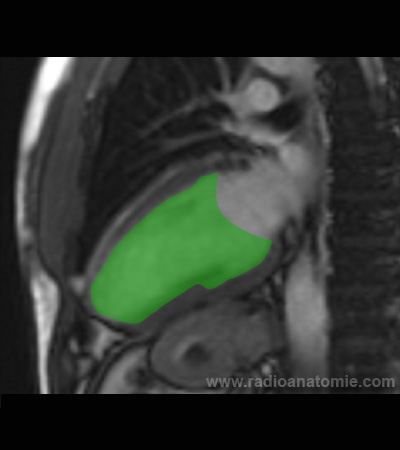

Radioanatomie et plans de coupe en IRM cardiaque

Coupe long axe 2 cavités

Ventricule gauche